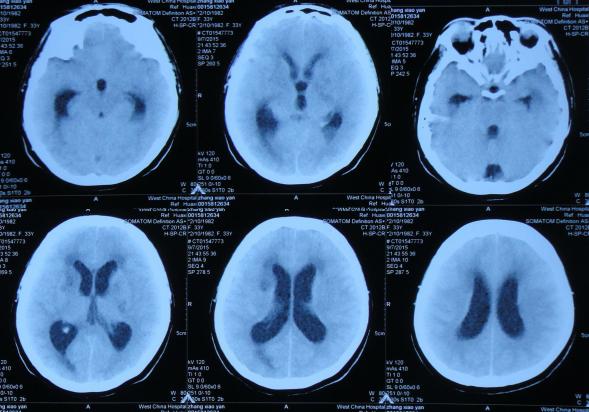

经头孢哌酮舒巴坦抗感染治疗1周后即2015年8月9日,仍间断头痛,发热有下降,但仍反复,但患者意识反变差,表情也变淡漠,查头部CT(图-2)。

图-2:2015年8月9日头部CT

第1家医院治疗13天后即2015年8月16日,查头CT:双侧侧脑室,三脑室及四脑室扩张(图-4),且给予腰穿检查,提示颅压高(脑脊液检查结果不详),给予相关对症治疗。

图-4:2015年8月16日头部CT

第1家医院治疗16天后即2015年8月19日,间断头痛,腰穿颅内压仍高,查头部CT示脑室进一步扩张(图-5)。

图-5:2015年8月19日头部CT